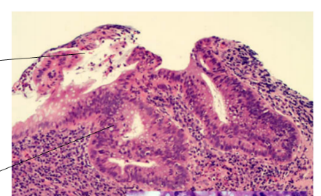

this image shows UC or CD? why?

UC

CD: